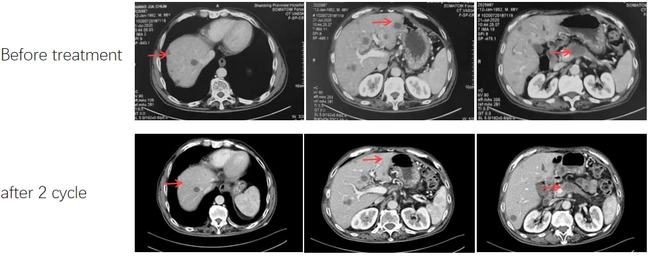

如下图所示,2020年7月至2020年9月,患者接受该联合方案治疗2个周期后,腹痛症状消失,NRS评分降至0-1分,CA199降至861ku/l,CEA降至77.77ng/ml,CT复查显示靶病灶总径较前缩小>30%,疗效评估为PR。

治疗前、治疗2周期后CT检查结果